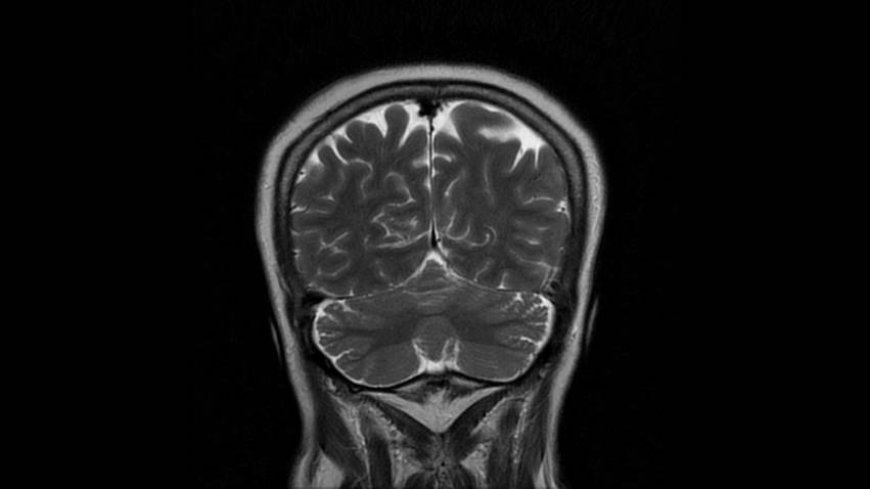

MRI of Brain

Coronal T2